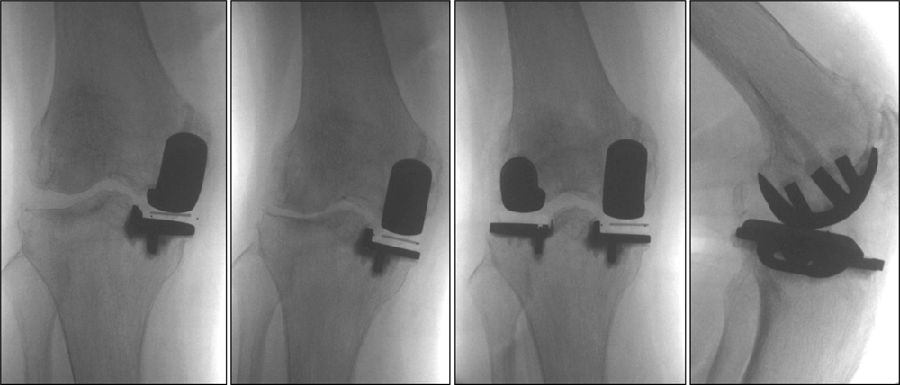

术前动力位片

术前透视。A.模拟负重位B.内翻应力位C.外翻应力位D.侧位